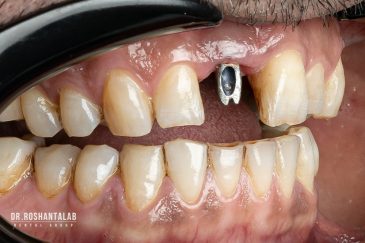

🔸 کاشت ایمپلنت دندان بدون درد

🔸کاشت ایمپلنت فلپ لس یا بدون جراحی و بدون بخیه زیر سه دقیقه

🔸 کاشت دندان یک روزه ( کشیدن و کاشت همزمان )

🔸 ایمپلنت دیجیتال و ساخت روکش دیجیتال